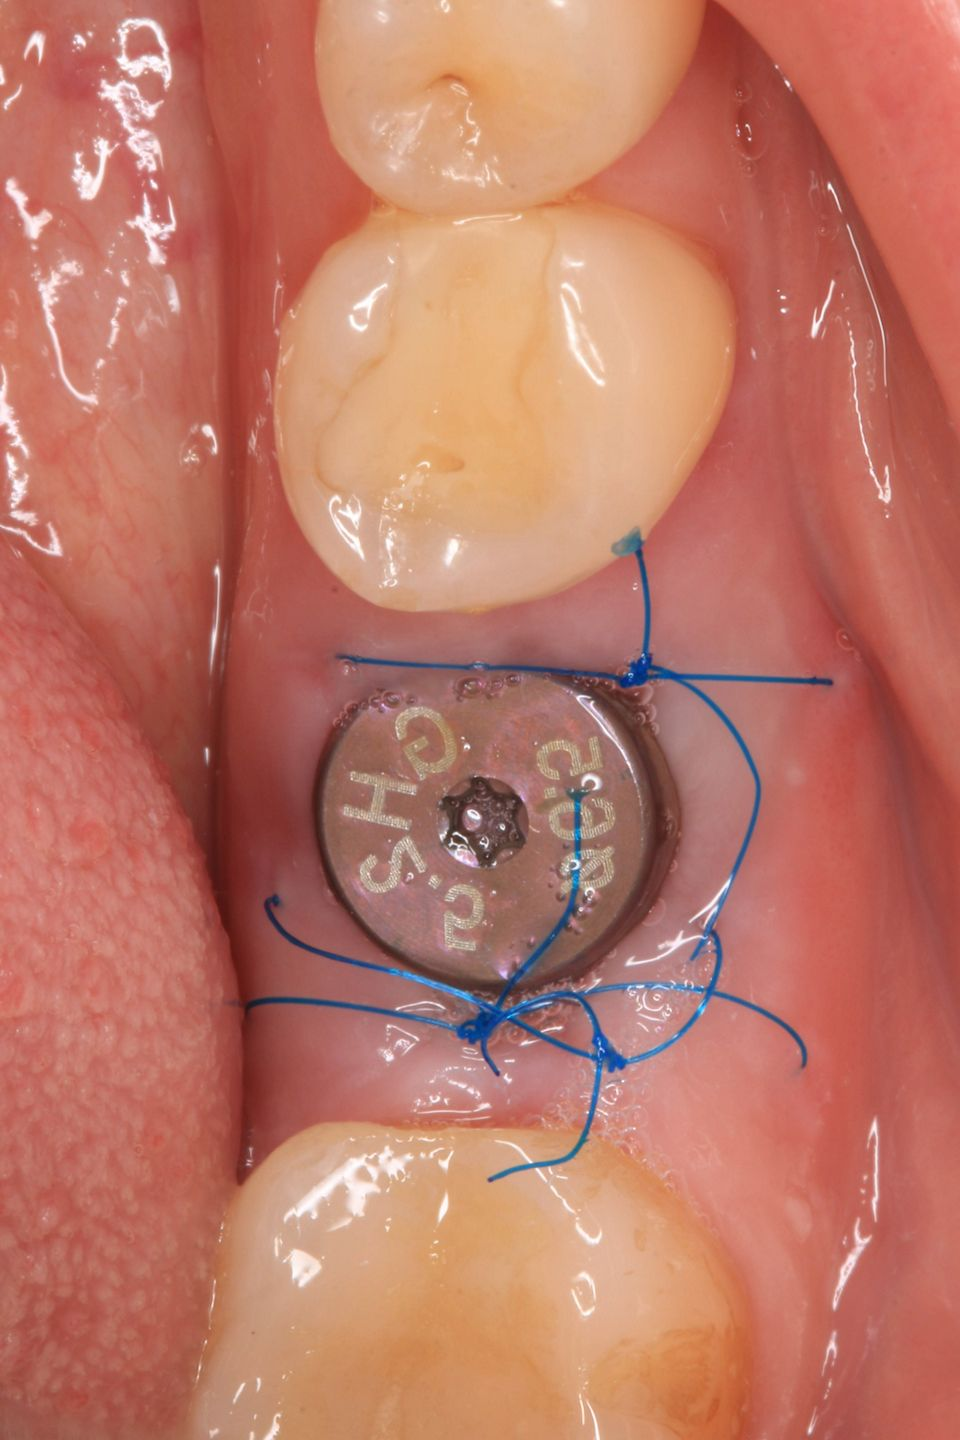

#36 牙的手术过程从局部麻醉和下牙槽神经阻滞开始。通过分割磨牙根实现无翻瓣反射的无创拔牙;从而保留肺泡壁和根间隔膜(图3-4)。仔细清洁牙槽,形成种植体路径并放置Straumann ® BLX 种植体 5.5 x 8 mm (图 5-7)。为了促进非浸没式愈合,将标准愈合基台连接至种植体。骨壁和种植体之间的间隙填充有同种异体骨材料颗粒(maxgraft®,botiss 生物材料,德国)。应用富含血小板的纤维蛋白(PRF)来实现适当的初步愈合。调整软组织边缘并用聚丙烯 6/0 缝合,使愈合基台暴露(图 8-9)。将粘性牙周Reso-Pac ®敷料(来自德国杜伊斯堡的Hager & Werken)放置在治疗区域上以协助愈合过程(图10)。

图6

手术后一周,拆线(图11-12)。在同一次就诊时,拍摄了垂直牙科射线照片(图 13),显示种植体处于正确的修复位置。四个月后,愈合基台被移除。粘膜外观表明植入物周围有稳定且健康的软组织,具有足够的生物宽度和光滑的出现轮廓(图14-15)。取印模,一个月后,将最终的氧化锆陶瓷牙冠拧到种植体上(图 16-18)。